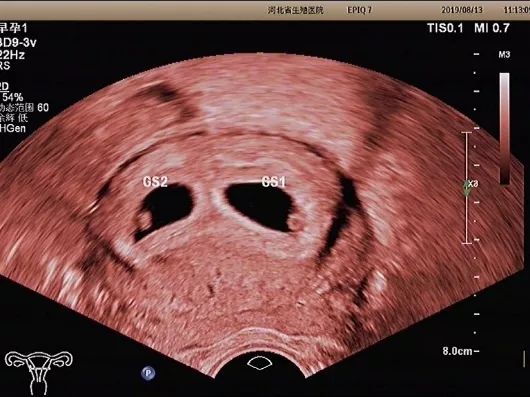

妊娠囊

确定妊娠囊是否在宫腔内,妊娠囊在宫腔内的位置、数目及大小。妊娠囊的大小可随孕周增长而增长。

子宫及双侧附件

观察是否合并子宫发育异常、子宫肌瘤,附件区是否有囊肿,或是否存在宫外妊娠。